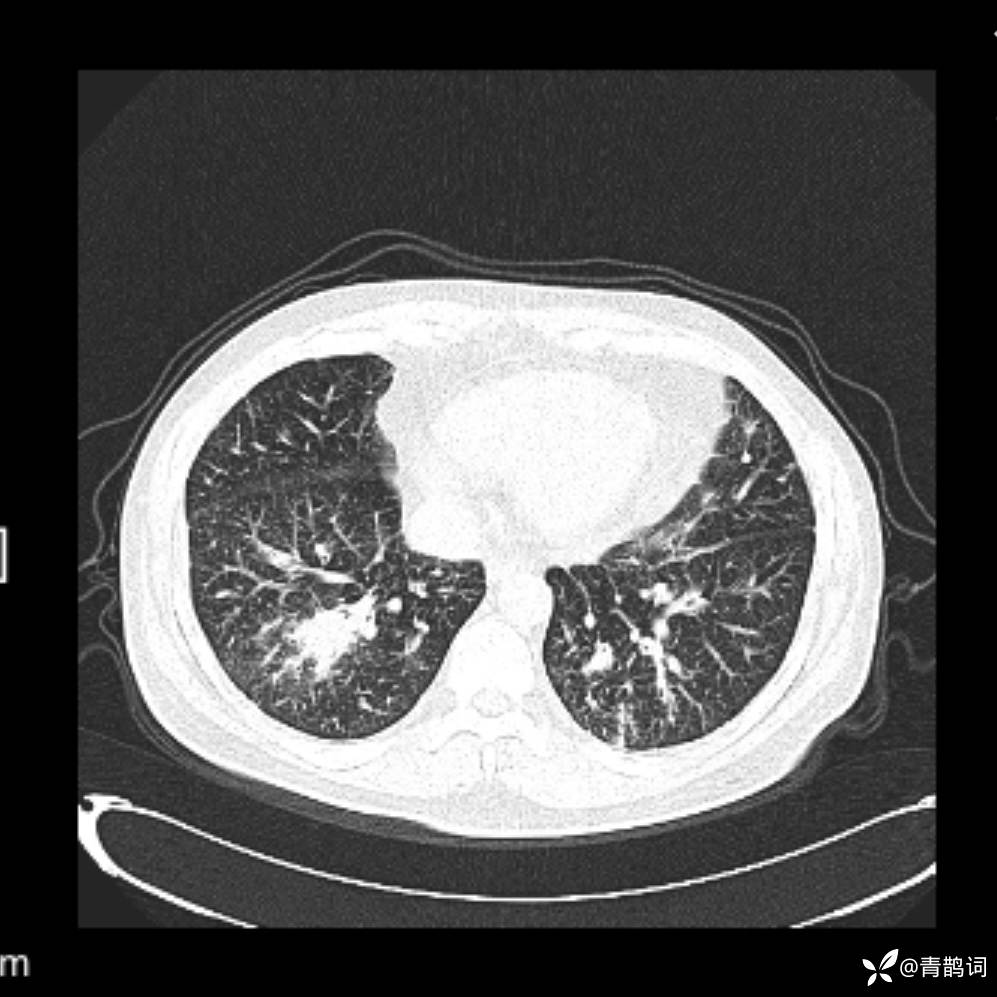

患者年龄:30岁。

患者性别:男。

简要病史:左颜面部肿胀2年,反复咳嗽咳痰,逐渐加重。

结合病史及影像学表现,期待评论区各位老师各抒己见~